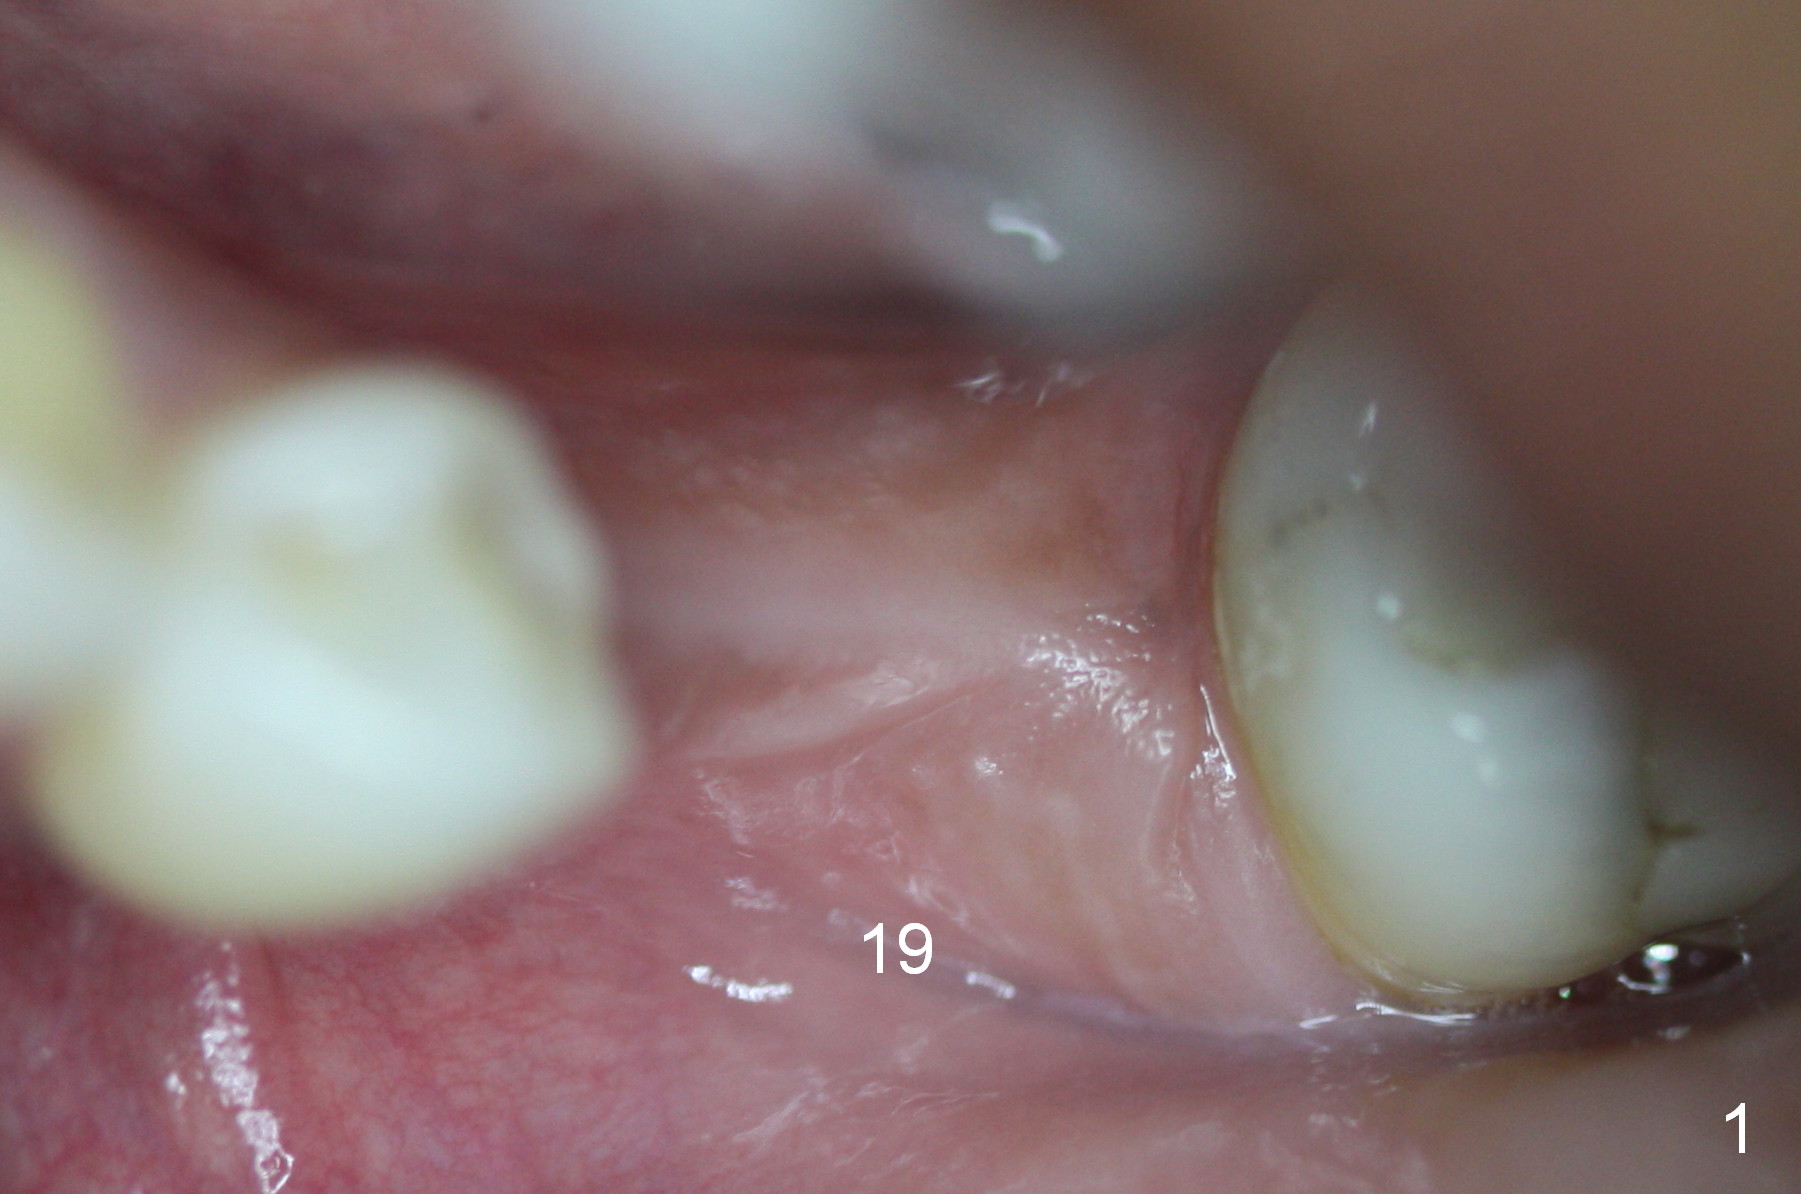

A 44-year-old black lady is a typical dental phobic. She has lost #19 for years with history of traumatic extraction. The ridge is atrophic (Fig.1). She is not comfortable with intraoral X-ray. So CBCT is taken. The coronal section shows that the bone density is low in the coronal ridge (Fig.2 arrowheads). It is difficult to determine the buccolingual width at crest; probably a 5.9x10 mm implant is appropriate (Fig.3). The most useful information from CT is height determination for the implant (Fig.4). The initial osteotomy depth is 10 mm (Fig.5); there is a large safety margin. There is a 2 mm clearance when a 4.5x12 mm implant is placed (Fig.6). Incision is sutured; a 8x4 (3) mm healing abutment is placed (Fig.7 arrowhead), followed by application of perio dressing. The latter remains stable 13 days postop thanks to the holding effect of the healing abutment (Fig.8 H). The wound has apparently healed when the dressing is removed (Fig.9). It appears that the edentulous space is extremely wide. The 4.5 mm implant may not sustain masticatory force. Limited orthodontic treatment appears to be necessary, using the implant as an anchorage to move the neighboring teeth (Fig.10 arrows). In fact the orthodontic treatment is not rendered. A crown is cemented 14 months postop. The cortical bone is thickened around the implant 15 months post cementation (Fig.11).